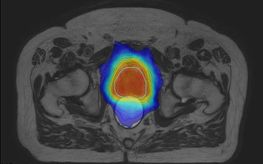

Die Universitätsklinik für Radioonkologie bietet zwei Studien (Mbase) für Patienten mit Prostatakrebs an. Die Behandlung erfolgt am MR-Linac, ein neues Geräte, das MR-Bildgebung mit einem Bestrahlungsgerät kombiniert. Dadurch ist der Tumor in Echtzeit während der Bestrahlung für den Arzt sichtbar und es kann schonender behandelt werden.

Seit der Behandlung des ersten Patienten am 20.09.2018 haben wir bis heute über 100 Bestrahlungen am 1,5 T MR-Linac Unity erfolgreich durchgeführt. Mit der Unterstützung durch Elekta und Philips konnten wir einen reibungslosen Ablauf der Echtzeit-MR-geführten Bestrahlung im täglichen Einsatz entwickeln. Bisher haben wir Patienten mit Metastasen im Beckenraum und in der Brustwand sowie Patienten mit Rektum- und Prostatakrebs behandelt. Bei allen Patienten war der Tumor und die angrenzenden gesunden Gewebe mit der hohen Auflösung der MRT am Bestrahlungsgerät sehr gut sichtbar.

Zusätzlich untersuchen wir mit speziellen MRT-Techniken das Therapieansprechen des Tumorgewebes, um in Zukunft die Therapie entsprechend anzupassen. Eine Übersicht über die Studienprotokolle am neuen MR-Linac finden Sie unter unserer Rubrik "Klinische Studien".

IMRT des Prostatakarzinoms: Ergebnisse der Tübinger Strahlentherapie auf DKK 2018

Auf dem diesjährigen Deutschen Krebskongress in Berlin wurden durch Dr. D. Wegener und PD Dr. A.C. Müller die Behandlungsergebnisse einer speziellen in Tübingen entwickelten Strahlentherapietechnik vorgestellt. Bei dieser Technik wird die Lagevariabilität der Harnblase, des Enddarms und der Prostata für jeden Patienten individuell in der Strahlentherapieplanung berücksichtigt (sog. Coverage-Probability Konzept). Die Ergebnisse zeigen eine hohe Tumorheilungsrate bei gleichzeitig sehr geringen Nebenwirkungen.

Neue Methode zur Strahlentherapie des Prostatakarzinoms in Tübingen ausgezeichnet

Oberarzt PD Dr. Arndt-Christian Müller aus der Universitätsklinik für Radioonkologie und sein Team haben für die ersten Ergebnisse zur MR-basierten bildgestützten Strahlentherapie des Prostatakarzinoms den Posterpreis auf dem Forschungskolloquium der Medizinischen Fakultät 2018 erhalten. In dieser Studie werden im Verlauf der Hormon- und Strahlentherapie wiederholt MRT-Untersuchungen durchgeführt. Diese Untersuchungen erlauben es, die Strahlentherapie auf Veränderungen der Prostata während der Therapie anzupassen und somit eine optimale Schonung der Harnröhre und es Enddarms sowie der Harnblase zu ermöglichen. Die Studie wird durch die Medizinische Fakultät Tübingen unterstützt. Die MRT-Untersuchungen erfolgen in Kooperation mit der Abteilung für Diagnostische Radiologie.